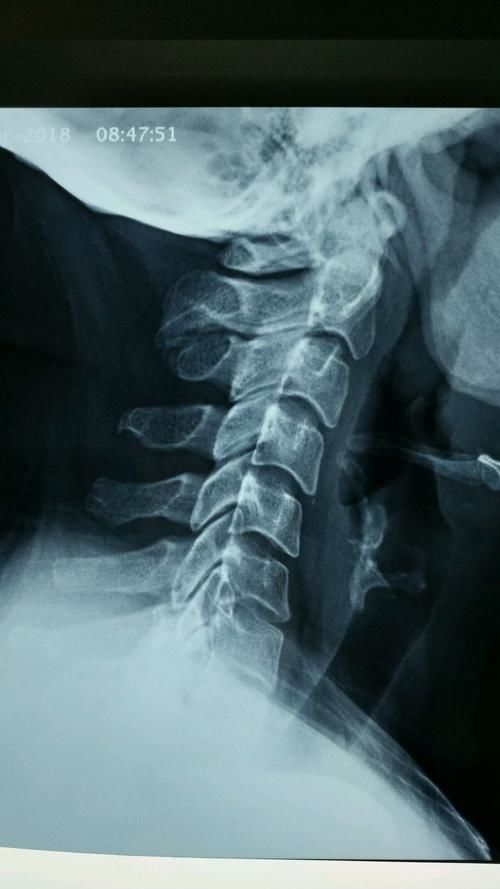

应用前后路联合手术成功治疗合并严重颈椎后凸畸形的颈椎病患者

图片尺寸2012x3094